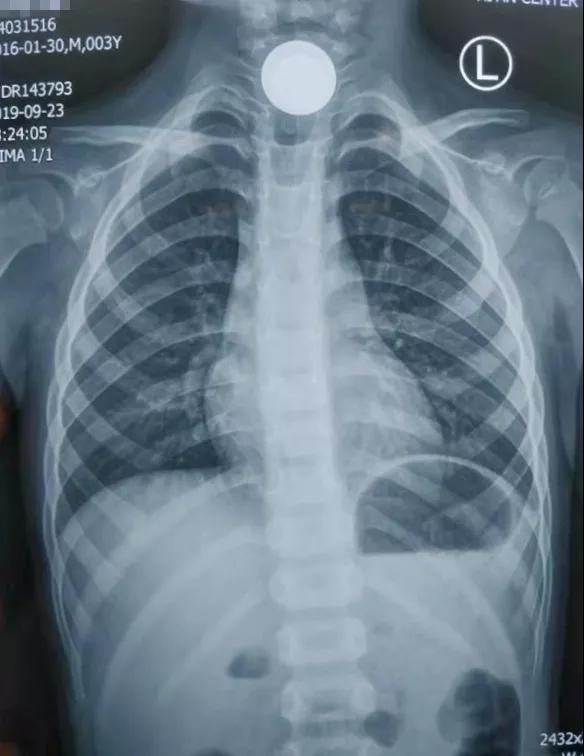

耳鼻喉科值班的主治医师王占江闻讯赶紧把孩子带进检查室,一问才知道,原来宝宝拿硬币玩,不小心将一枚一块钱硬币咽下去卡嗓子里了。孩子难受指着嗓子不停哭泣,痛苦的都说不清话了,家长心急如焚,经过详细的专科检查,王医生赶紧让孩子去拍了片子,出乎意料的是——宝宝食道里竟然卡顿了两枚硬币,一枚一元硬币一枚一角硬币!